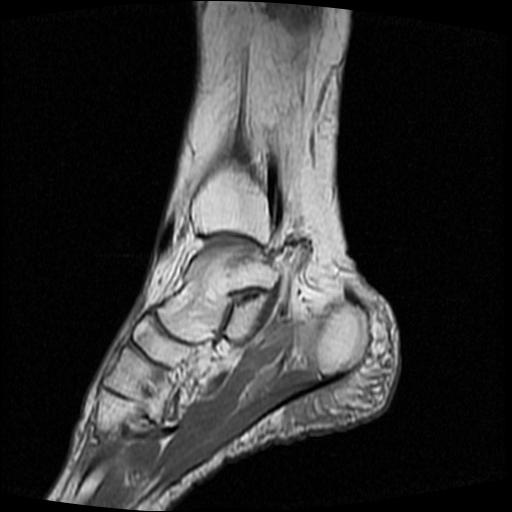

标题: MRI0968:女性,70岁,跟骨信号异常 [打印本页]

标题: MRI0968:女性,70岁,跟骨信号异常

女性,70岁,右侧跟骨疼痛2个月,负重时加剧,不负重时不疼。

胫骨下段,跟骨、距骨可见斑片状异常信号区;考虑:转移瘤

跟骨长t1长t2信号异常,边缘模糊(肿瘤一般边界清楚,故肿瘤不考虑),压脂像呈高信号--骨髓水肿(炎症?)。